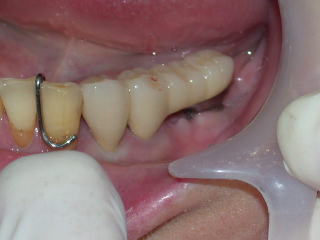

口腔内に試適し、色や形なども患者さんに確認してもらいます。

咬み合わせの状態をチェックし、装着します。

次回、セメントが完全硬化後、再度咬み合わせなどををチェックし、歯間ブラシを主にブラッシング指導を行います。

今回のインプラントをしばらく使っていただき、調子がよければ、左上、右下もインプラントを希望です。

右下5番目が保存不可能ですので抜歯予定、インプラント植立は半年ほど先の予定です。

左上前歯部はインプラントを植立し、ロングスパンのブリッジが折れないようにして、入れ歯から固定式に変更する予定です。